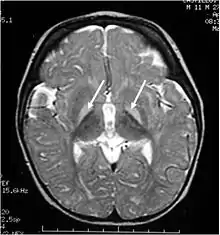

| Brain MRI. Hyperintense basal ganglia lesions on T2-weighted images. | |

These impairments are associated with lesions in the basal ganglia, auditory nuclei of the brain stem, and oculomotor nuclei of the brain stem. Cortex and white matter are subtly involved. Cerebellum may be involved. Severe cortical involvement is uncommon.